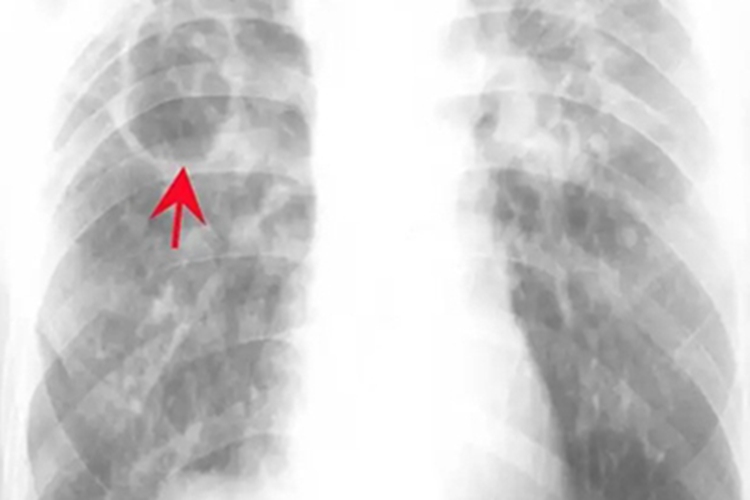

急性血行播散型肺结核:表现为由肺尖至肺底呈大小、密度和分布不均匀的粟粒状结节阴影,结节直径2mm左右。